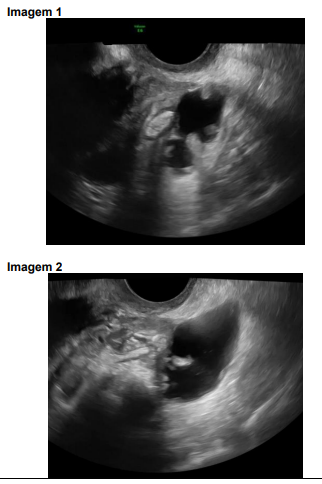

Nas imagens 1 e 2 estão representados dois sinais ecográficos de hidrossalpinge.

As imagens ecográficas representam, respectivamente: